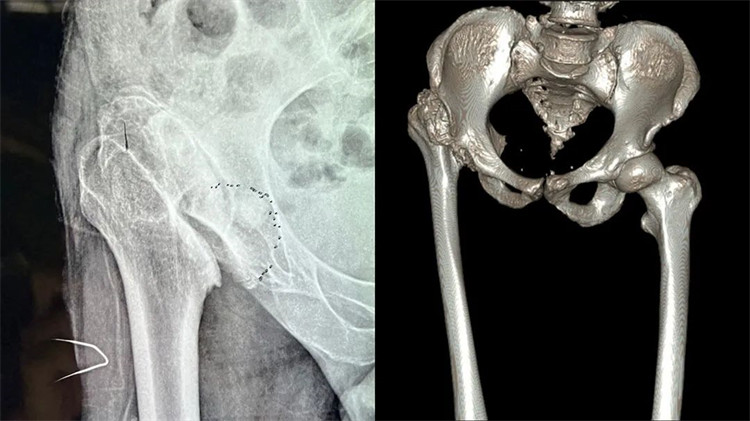

患者術(shù)前嚴(yán)重變形的髖關(guān)節(jié)

周大伯來(lái)院后經(jīng)X線片及CT檢查,發(fā)現(xiàn)右側(cè)股骨頭壞死、形態(tài)失常,已經(jīng)完全脫離正常的位置,且很難找到真臼,右側(cè)髖臼形態(tài)失常、部分骨質(zhì)缺失。想要徹底解決周大伯的問(wèn)題,需要進(jìn)行右側(cè)人工全髖關(guān)節(jié)置換。但周大伯患病50余年,且有過(guò)失敗的手術(shù)病史,髖關(guān)節(jié)感染后遺癥,髖關(guān)節(jié)脫位,長(zhǎng)短腿5公分,手術(shù)難度系數(shù)較大,不能有任何偏差,稍有偏差,嚴(yán)重者可影響手術(shù)效果,留下后遺癥。